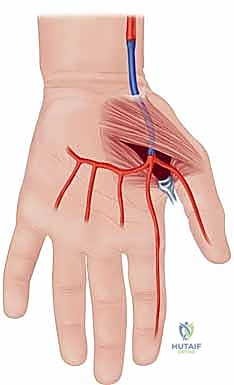

Arterial Architecture and the Palmar Arches

Before a single incision is conceptualized, an exhaustive mastery of the hand's vascular architecture is paramount; in this anatomical theater, precision is synonymous with prevention. The primary arterial inflow to the hand is derived from the radial and ulnar arteries, which originate from the bifurcation of the brachial artery at the antecubital fossa. The ulnar artery, typically the dominant vessel, courses distally to form the superficial palmar arch, located superficially within the mid-palm, deep only to the palmar aponeurosis. This arch serves as the major arterial conduit supplying the ulnar aspect of the digits, giving rise to the common digital arteries.

The radial artery, after traversing the anatomical snuffbox and piercing the first dorsal interosseous muscle, primarily forms the deep palmar arch. This structure lies more proximally and deeply within the palm, resting directly upon the metacarpal bases and interosseous muscles, and predominantly supplies the radial aspect of the hand, including the thumb and index finger. In approximately 80% of the patient population, these two arches are in continuous communication, forming a complete palmar arch system that provides robust, redundant collateral circulation. However, the presence of an incomplete arch significantly amplifies the risk of catastrophic ischemia should one primary inflow vessel become compromised. Furthermore, anatomical variants such as a persistent median artery—which accompanies the median nerve through the carpal tunnel—can contribute significantly to digital perfusion and must be identified during preoperative mapping.

The Flatt Digital Sympathectomy is the cornerstone procedure for medically refractory Raynaud's phenomenon with patent inflow. The objective is the precise mechanical ablation of the sympathetic nerve fibers traveling within the arterial adventitia. Under high magnification, the common digital arteries and their proper digital branches are identified as they emerge from beneath the superficial palmar arch.

The first critical step is the isolation of the digital artery from the adjacent proper digital nerve. These structures are intimately bound by delicate fascial bands. Using fine micro-forceps and micro-scissors, the surgeon meticulously separates the artery from the nerve over a distance of 1.0 to 2.0 cm. Extreme vigilance is maintained to avoid any traction or direct trauma to the nerve, which could precipitate a painful postoperative neuroma.

Once the artery is isolated, the adventitial stripping commences. The surgeon stabilizes the arterial wall with one set of non-toothed jeweler's forceps. With a second set of forceps, the thin, translucent outer adventitial layer is grasped. Using a highly controlled, peeling motion—akin to removing the thin skin from a grape—the adventitia is stripped circumferentially from the underlying muscularis media.

As the adventitia is removed, the visual appearance of the artery changes dramatically; it transitions from a slightly opaque, tethered vessel to a smooth, highly translucent, and often visibly dilated conduit. This visual cue is the hallmark of a successful sympathectomy.

Concurrently, the surgeon must identify and sharply divide any microscopic tethering branches or fine neural connections bridging the proper digital nerve and the arterial wall, as these frequently carry aberrant sympathetic fibers.